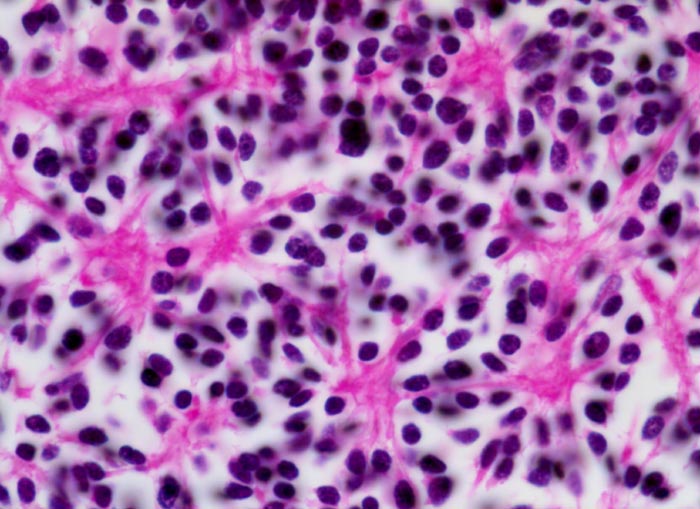

Wegen der hohen Zelldichte und der hohen Kern-Zytoplasmarelation erscheinen die Tumoren in der HE Färbung blau. Medulloblastome müssen differentialdiagnostisch von morphologisch ähnlichen kleinzelligen undifferenzierten Karzinomen und Lymphomen abgegrenzt werden. Das klassische Medulloblastom besteht aus dicht gepackten Zellen mit runden bis ovalen oder karottenförmigen stark hyperchromatischen Kernen umgeben von wenig Zytoplasma. Runde Zellen mit weniger dichtem Chromatin sind oft beigemischt. Zahlreiche Mitosen, flächenhafte Nekrosen und Apoptosen sind typisch. In weniger als einem Drittel der Fälle findet man die typischen Homer-Wright Rosetten. Diese bestehen aus ringförmig angeordneten Tumorzellkernen um ein fibrilläres Zentrum aus Zytoplasmafortsätzen.

• Homer-Wright Rosetten aus ringförmig angeordneten Tumorzellkernen um ein fibrilläres Zentrum aus Zytoplasmafortsätzen.

• Monomorpher Zellrasen mit hyperchromatischen ovalen oder karottenförmigen Zellkernen.

• Kaum erkennbares Zytoplasma.